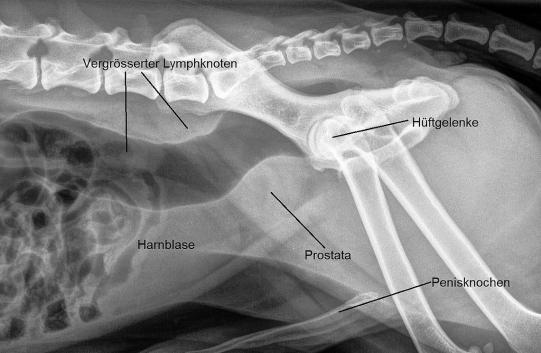

Zur Abklärung eines möglichen Blasen- oder Prostataproblems wird zuerst ein Röntgenbild angefertigt. Hier sieht man, dass die Prostata vergrössert ist (was bei einem kastrierten Rüden ungewöhnlich ist) und der Enddarm vor dem Beckeneingang etwas gegen unten gedrückt erscheint - möglicherweise wird dies durch vergrösserte Lymphknoten in dieser Gegend bewirkt.